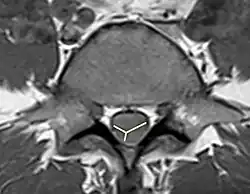

As the non-contrast CT and spine CT angiography are ineffective in imaging modalities, doctors use MRI to confirm the diagnosis. MRI findings, including pencillike hyperintensities on T2-weighted sagittal images and "owl's eyes" or "snake eyes" sign on T2 axial images, indicate the infarction is predominately in the watershed area of the gray matter of ventral horn (anterior spinal artery infarct).[10] Also, posterior paramedian triangular hyperintensity in T2 hyperintensity indicates posterior spinal artery infarct. On a T1 sequence, we may also observe a cord expansion and a decreased signal.[18] However, traditional MRI may show no abnormality especially for those patients in the acute phase.[8] DWI is very sensitive for early detection of spinal cord infarction and shows a typical high signal intensity.[19]

To identify the hematoma in the spinal cord, MRI with and without gadolinium enhancement is the preferred choice.[9] CT is also used to identify the hemorrhage and provide evidence for pathological analysis. Complete spinal MRI with MR angiography is used when patients with subarachnoid hemorrhage without the intracranial etiology.[20] As the evaluation of the need for intradural interrogation is important, it is necessary to differentiate between subdural and epidural hematomas. Based on the location of the hematoma, use both axial and sagittal images of MRI to identify the boundary between hematoma and fat.[7] An inverted Mercedes-Benz sign shows the spinal subdural hematoma on the axial image.[21]